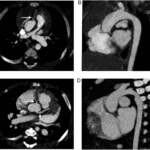

Clinical Implementation of PCCT In the last 5 years, more than 200 scientific articles have been written on photon-counting CT…